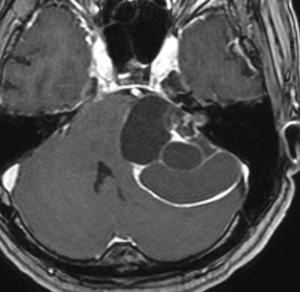

腫瘍が嚢胞性拡大で大きくなって,腫瘍内出血して,閉塞性水頭症になって意識障害を生じた患者さんです。このような事態になると臨時手術で腫瘍を摘出します。

大きなのう胞性聴神経腫瘍です。いくつかの袋が重なって腫瘍を形成しています。橋や延髄(脳幹部)が変形して,第4脳室がつぶれて閉塞しています。袋の周りが白く線状に造影されているのですが,この袋の壁だけに腫瘍細胞がありますから,これを剥がすように摘出します。顔面神経が薄くなって袋の壁にくっついているのですが,袋を破ってくしゃくしゃにすると顔面神経の位置が変わってしまって,顔面神経を損傷することがあるので要注意です。のう胞性聴神経腫瘍の方が顔面神経麻痺の後遺症の頻度が高いという報告もあるくらいです。この患者さんは迷走神経と舌咽神経の圧迫も強くて,ご飯を飲み込むことが難しくなっていました(嚥下障害)。

また,この患者さんは急に容態が悪くなって意識障害となりました。何故なら腫瘍の内部で出血したからです(黄色の矢印の部分)。第4脳室が詰まって閉塞性水頭症になって側脳室が拡大しています(右の画像)。